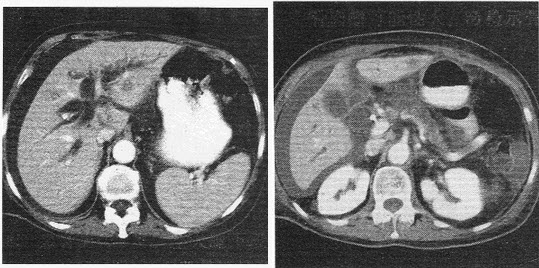

43������ѡ���� �����У�44�ꡣ���ϸ���ʹ���꣬���ذ��ϸ�������1���£��鸹�͡��ɲ���ģ���Ż�¡���к����С�������������½�5kg���������Ҹβ�ʷ���ꡣ���壺T36.7�棬P78�Σ��֣�R18�Σ��֣�BP110��70mmHg��ȫ��Ƥ����Ⱦ����Ĥ��Ȼ�Ⱦ����ƽ�������ϸ����������ϸ�ѹʹ�������ţ������״�����5cm����Ե�ۣ����ͣ��д�ʹ��Ƣδ��������ߵ����������ƶ������������Ͻ�ߵ���ڵ����䣬����ߵʹ�����ﳦ����8�Σ��֡�������飺Hb89g��L��WBC5.6��109��L��ALT84U��L��AST78U��L��TBIL30��nol��L��DBIL10��mol��L��ALP188U��L��GGT64U��L��AFP880ng��ml��CEA24mg��ml��B��������Ҷʵ����ռλ�Բ���8cm��������ܲ����š�

������鷢�ָ���ҶԼ3cm�飬AFP�������ߣ���Զ��ת�ƣ��ι��ܻ������������߾ܾ�����������ʵ������ǣ���

A.����

B.����Ҷ��X������

C.��ҩ����

D.ȫ������

E.������